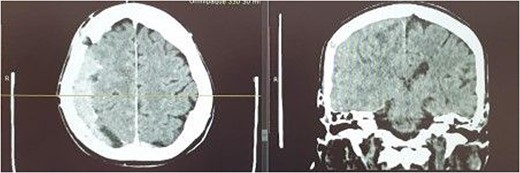

A 65-year-old man was admitted to the ED of our institution in April 2022. The patient presented with symptoms such as headaches, nausea, vomiting, vertigo, diplopia, fatigue as well as numbness of his left lower extremity. Furthermore, the patient had a history of metastatic prostate cancer and had discontinued chemotherapy 3 months before. In March 2022 underwent right chronic SDH evacuation via burr hole trephination. On examination he was fully conscious and verbally responsive, he did however experience sensory disturbances in his left upper and lower extremity. A non-contrast and contrast enhanced CT was performed initially showing an isodense right sided mass enhancing after contrast admission of 14 mm thickness with midline shift of 3 mm. The consulting radiologist diagnosed a chronic SDH (Fig. 1). The patient was admitted to the neurosurgical ward and was qualified for trephination under general anesthesia. Intraoperatively, dura mater was opened and tumorous mass was detected. Tumor was adherent to underlying brain tissue (Fig. 2). Partial resection was performed. Histopathologic samples were taken. Postoperatively, the patient was discharged home on Day 8 in fair general condition. Histopathologic examination was consistent with metastatic adenocarcinoma of the prostate. After oncological consultation the patient underwent radiation treatment. Due to advancement of neoplastic disease and gradual worsening of the patient’s general condition he died a month after surgery.